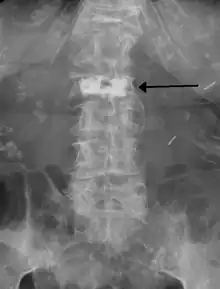

Cement in a vertebra as seen on plain Xray.

Kyphoplasty is a variation of a vertebroplasty which attempts to restore the height and angle of kyphosis of a fractured vertebra (of certain types), followed by its stabilization using injected bone cement. The procedure typically includes the use of a small balloon that is inflated in the vertebral body to create a void within the cancellous bone prior to cement delivery. Once the void is created, the procedure continues in a similar manner as a vertebroplasty, but the bone cement is typically delivered directly into the newly created void.[3]